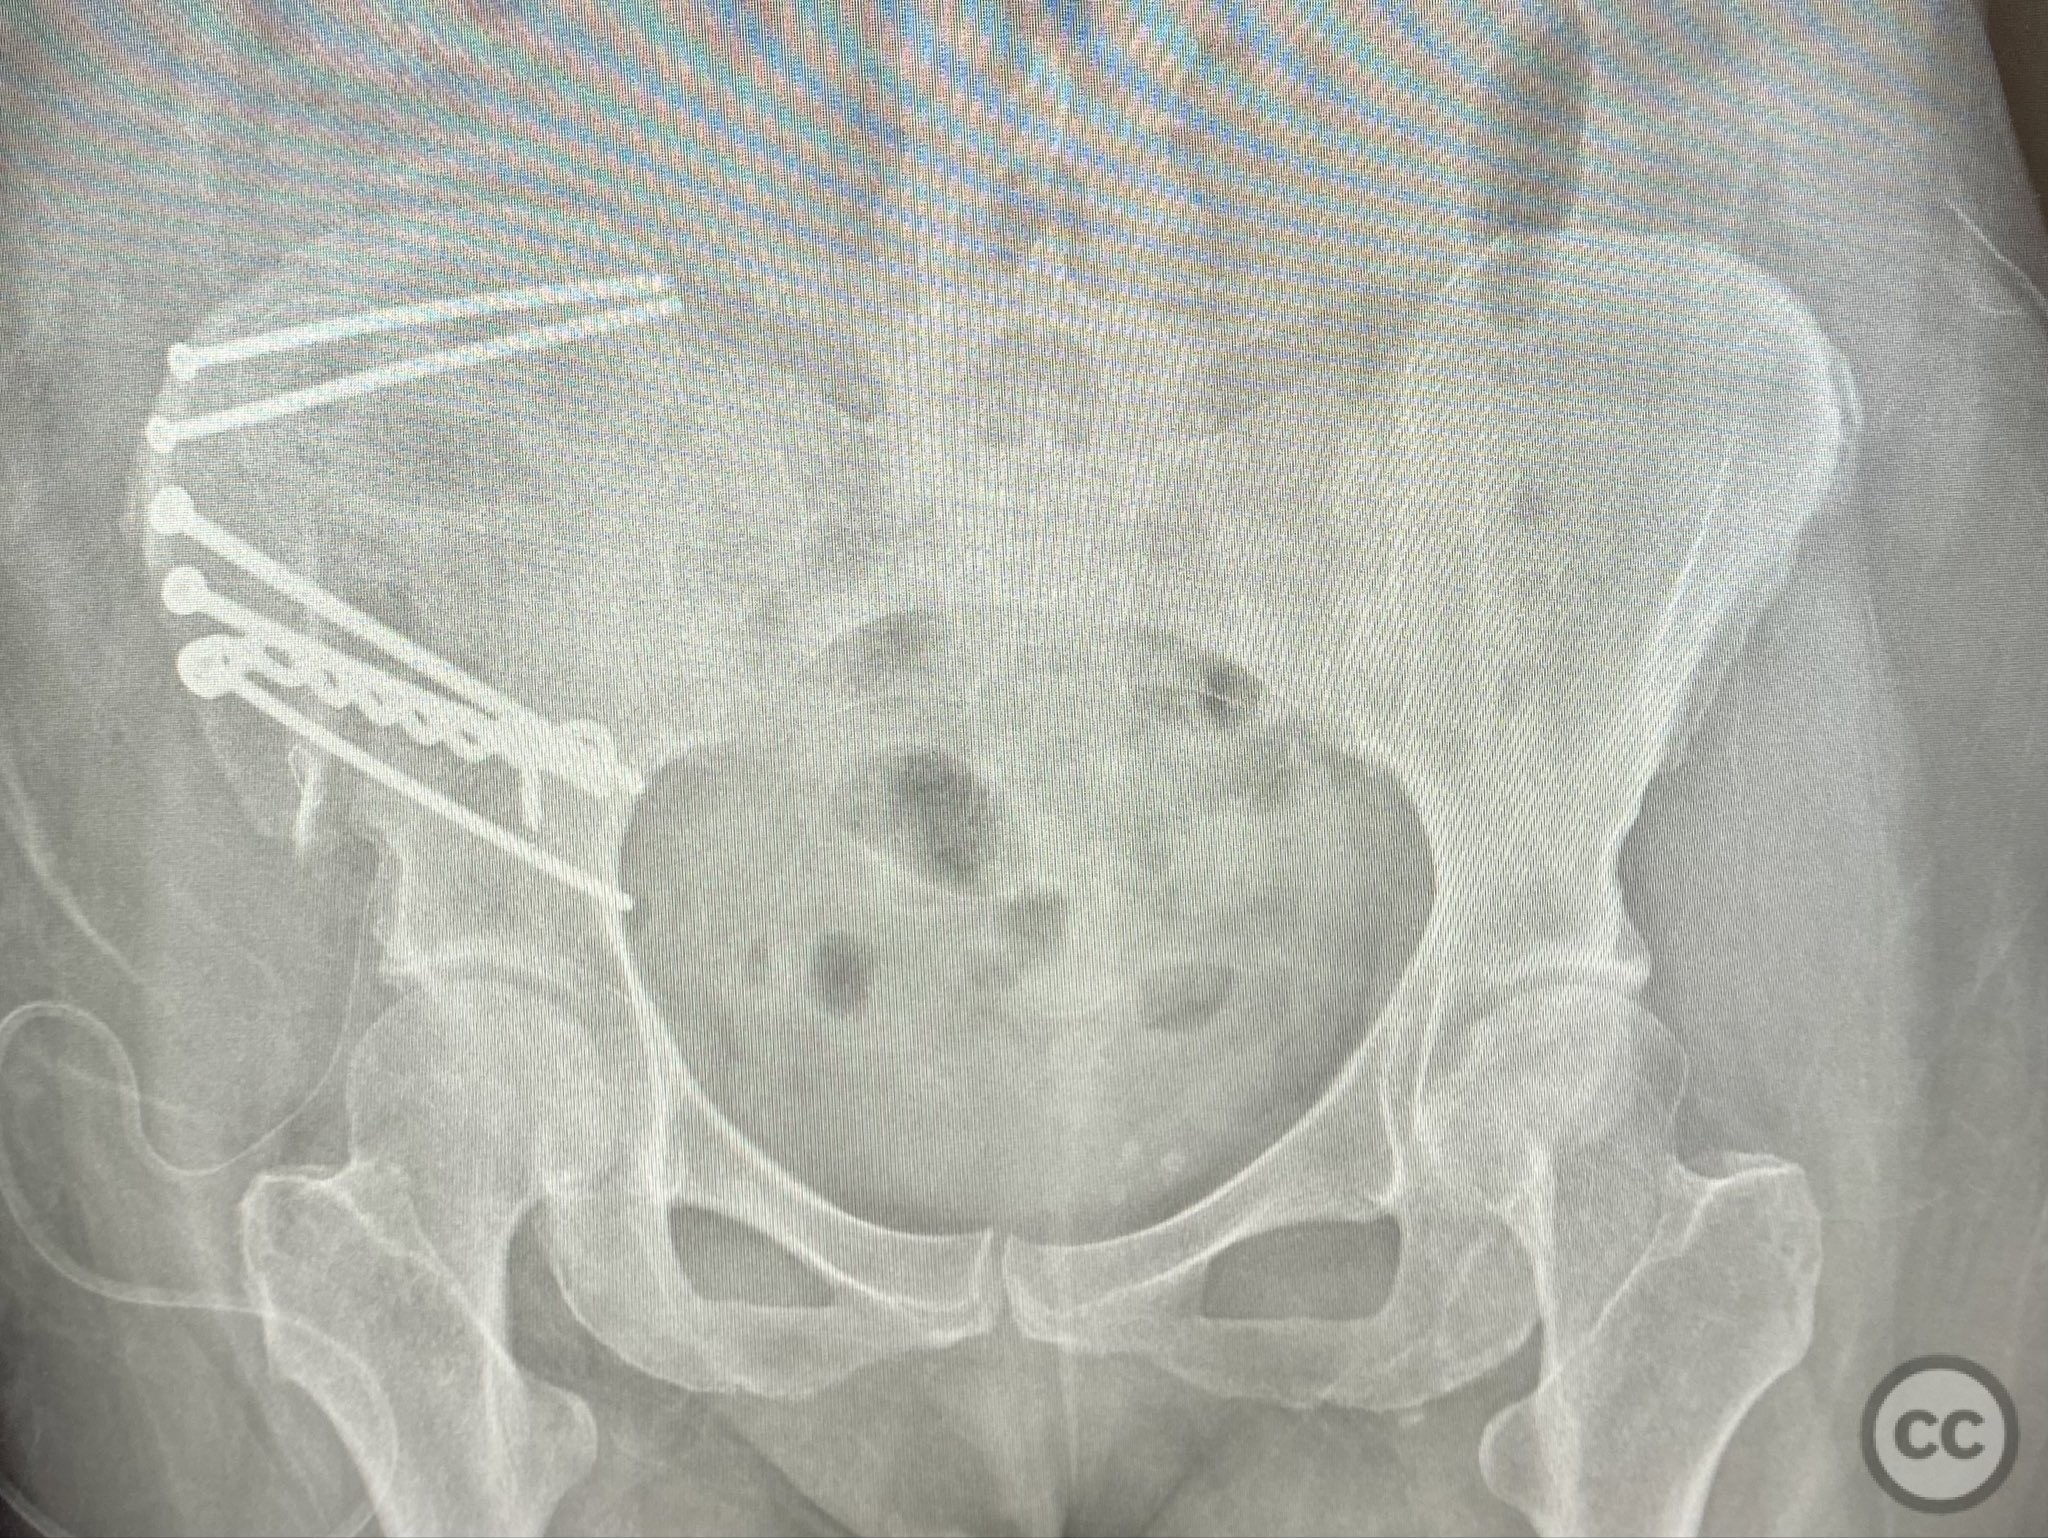

The comminuted fragments were mobilized and reduced using pointed reduction forceps and ball-spike pushers under direct vision. Lag screws were placed transversely between the inner and outer cortical tables of the ilium to achieve interfragmentary compression across major fracture lines. A pre-contoured reconstruction plate was then applied along the crest and tensioned to supplement the lag screws, providing additional stability across zones of comminution. The expanded exposure facilitated thorough cleaning of hematoma and debris, precise reduction, and secure clamp placement during fixation.

Orthopaedic implants used:   3.5mm cortical lag screws; pre-contoured 3.5mm reconstruction plate